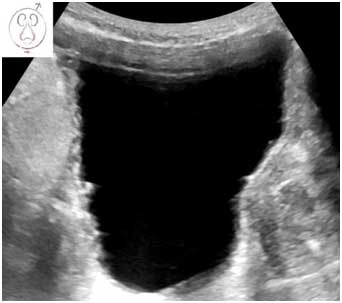

Την τελευταία δεκαετία υπάρχει ιδιαίτερο ενδιαφέρον για τη μέτρηση του πάχους του τοιχώματος της κύστης που αποτελεί μία έμμεση μέτρηση της μάζας του εξωστήρα μυός. Οι υψηλές εξωστηριακές πιέσεις κατά την ούρηση σε άνδρες με υποκυστικό κώλυμα οδηγούν αρχικά σε αύξηση του μεγέθους του λείου μυός (υπερτροφία/υπερπλασία του εξωστήρα) που θα εξελιχθεί σε μείζονες μεταβολές σε πιο προχωρημένα στάδια, όπως ίνωση, υπερλειτουργικότητα και ελαττωμένη λειτουργική χωρητικότητα.